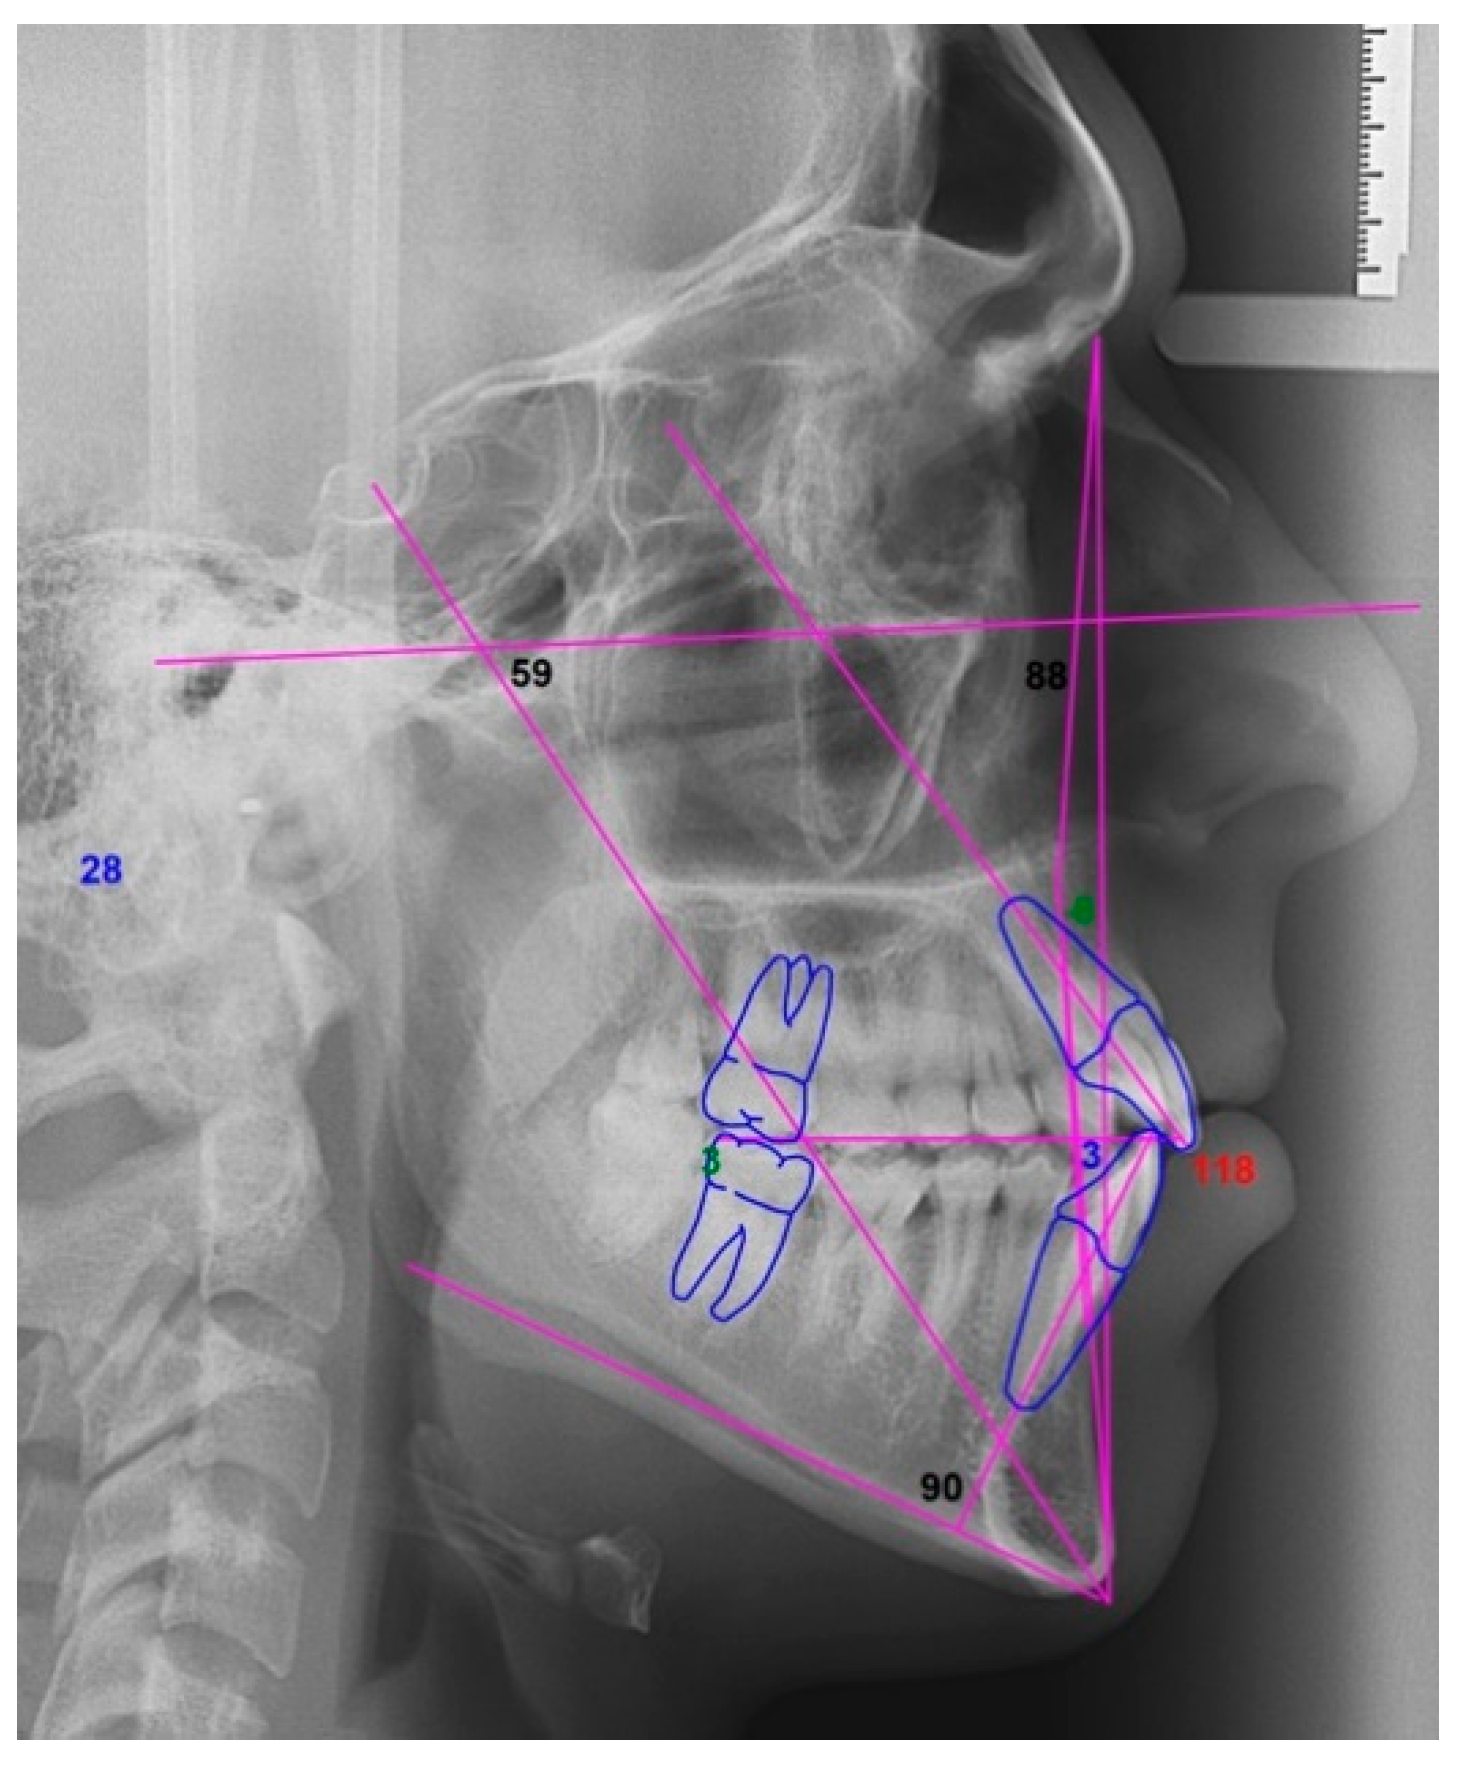

2.2. Orthodontic Planning

2.3. Surgical Procedure